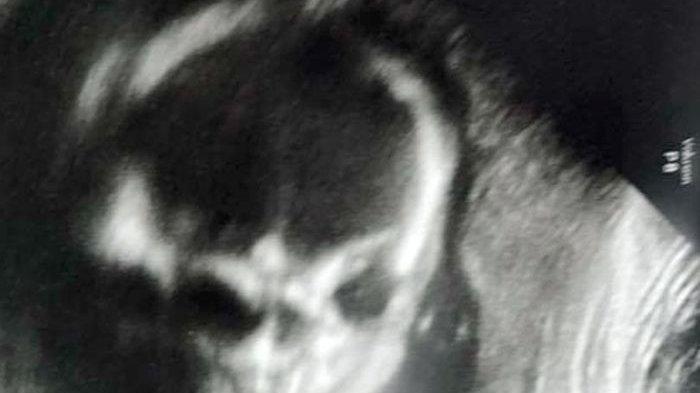

Menurut laporan Daily Mirror dikutip dari Intisari, pada Senin (12/8/19), Jessica Woods (23) asal Oklahoma, Amerika Serikat, mendapati bayinya terlihat hanya memiliki kerangka melalui hasil pemindaian ultrasonic.

Padahal waktu itu usia kehamilannya sudah menginjak 21 minggu lima hari, yang termasuk cukup tua.

Bayi itu tampak seperti kerangka pada hasil Ultrasonography (USG) yang ia bagikan.

Jessica mengatakan, "Awalnya saya hanya melihat USG normal, dan semuanya baik-baik saja.".

"Tapi kemudian dia perlahan memutar kepalanya dan menghadap kami, itu benar-benar menyeramkan," katanya.